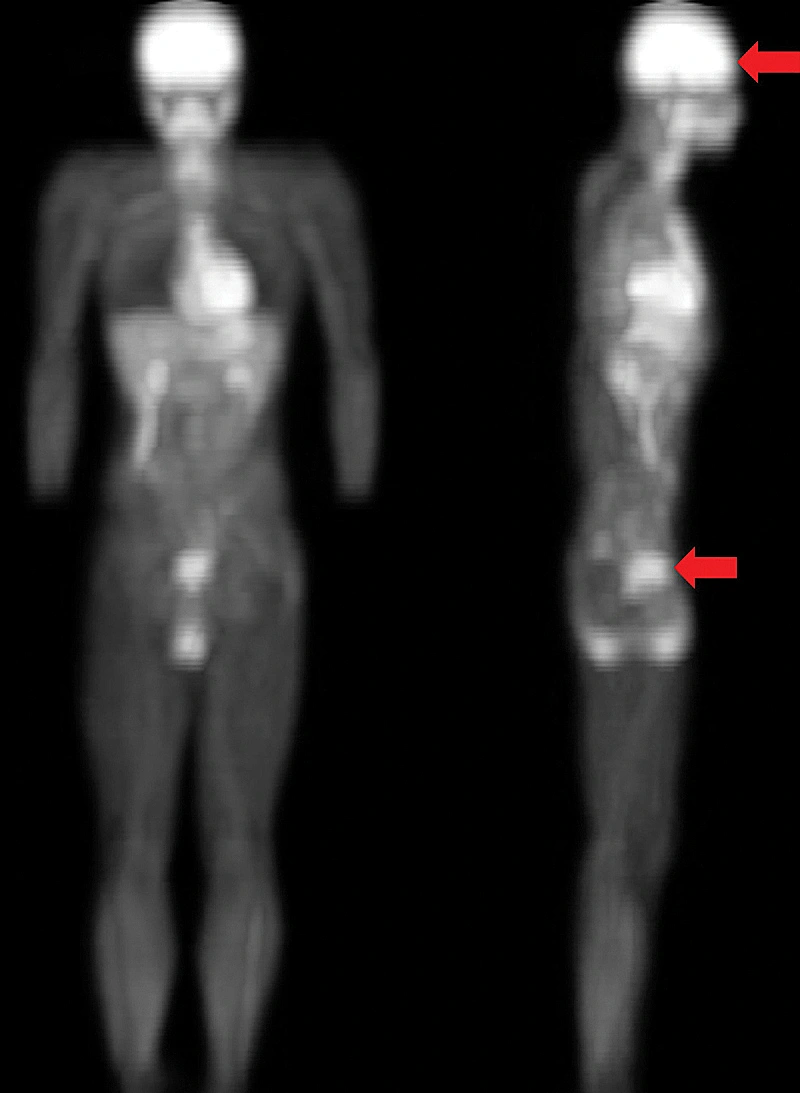

חשוב לציין כי על אף שאכן מדובר במחקר מדעי אמיתי, בעל ביקורת עמיתים, סריקות מוח ובדיקות קוגניטיביות, המחקר התמקד בספורטאים בלבד, כך שאין לדעת אם אותן השפעות חלות על כולם. כך או כך החוקרים ממליצים לעשות קקי בין 60 ל-90 דקות לפני קבלת החלטות חשובות.